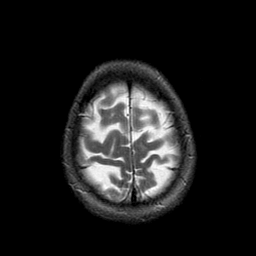

Metastatic Adenocarcinoma of the Colon: T2-weighted MR -- Slice #21

[Home][Help][Clinical] Slice 21